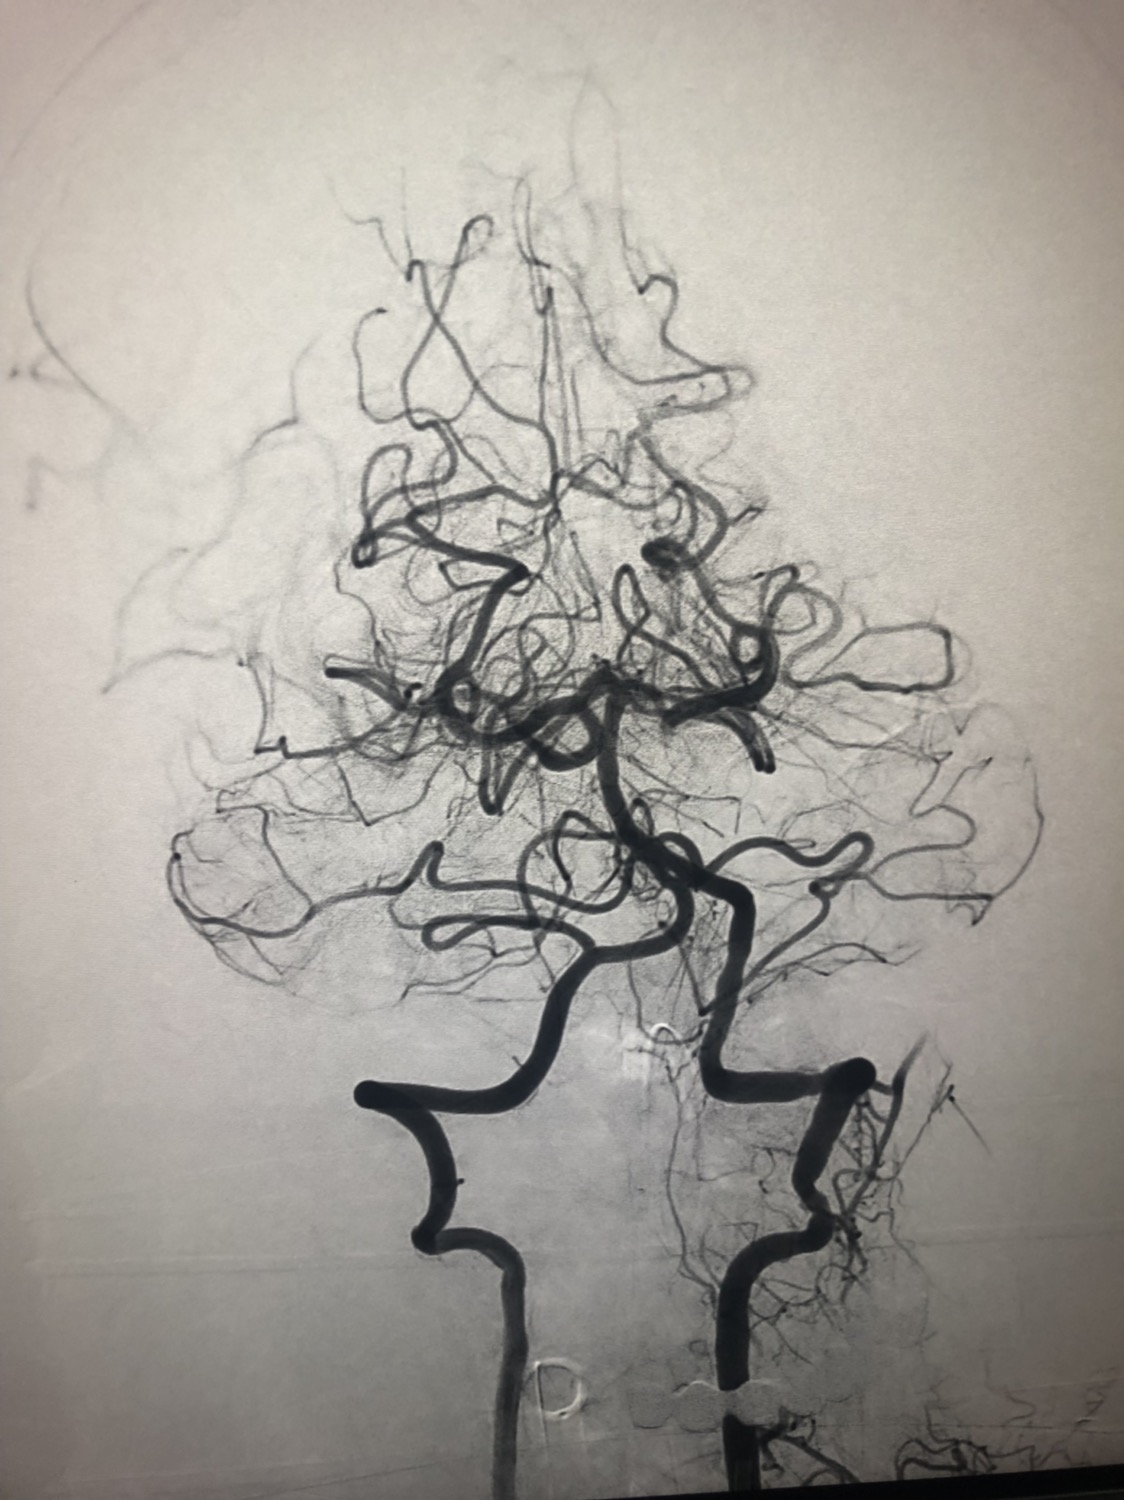

1周前房颤栓塞肱动脉,切开取栓后服用利伐沙班3天。突发偏瘫凝视3小时。上台看M3、A3血栓,国产普威森6f125cm抽吸导管高到位结合尼科3x20mm小支架,结合精细操作,m3和a3的血栓也可以轻松取出。不刺激血管。加造影射线16min两次取栓两个血管再通。

柔软的国产普威森微导管,高到位。

3x20mm的国产reco支架,适合分支血管取栓。